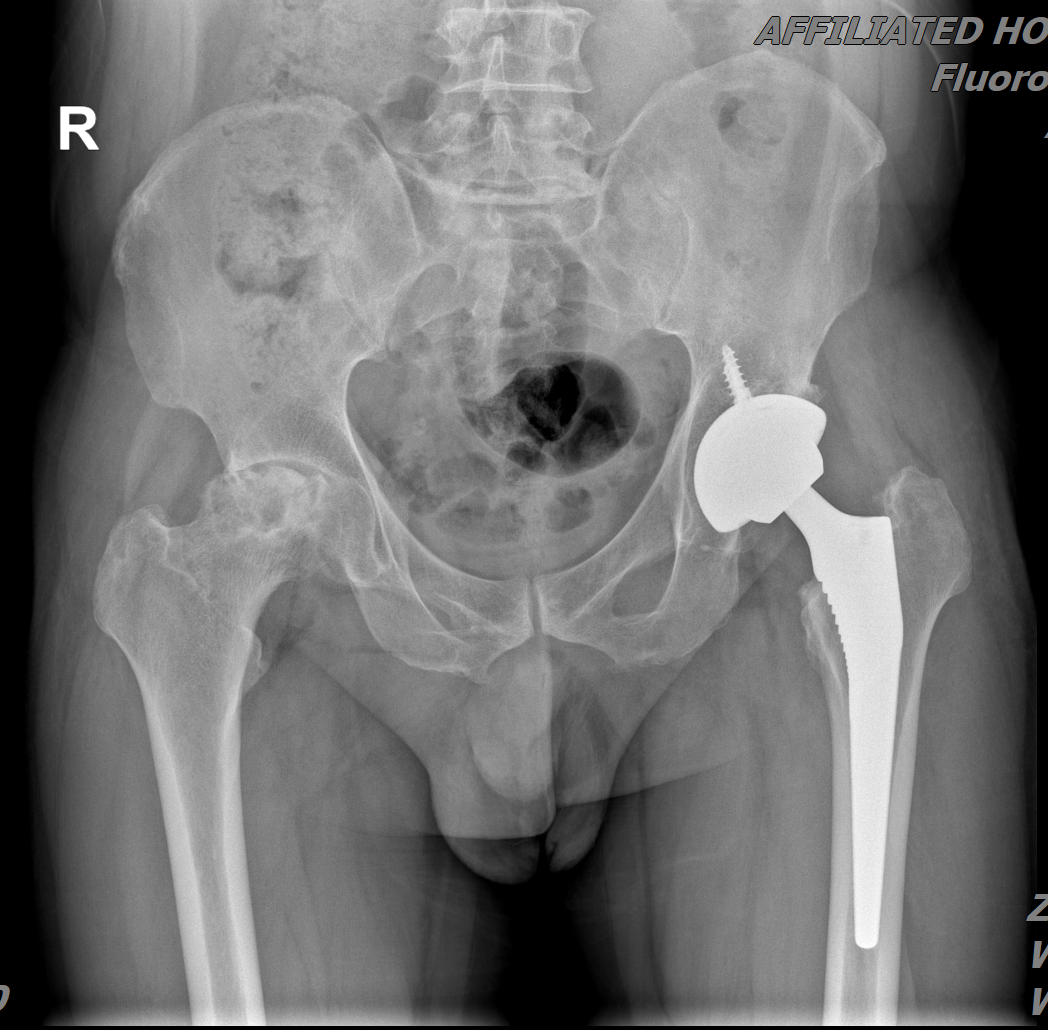

2025年2月25日,50岁的*先生因股骨头坏死,在川北医学院附属医院接受左侧髋关节置换术。术中,医疗团队截取多余的骨组织(通常这部分组织以医疗废弃物丢弃),送至自体骨组织专业储存机构(四川骨源生物科技有限公司),利用其-196℃深低温储存技术进行保存。同年7月4日,*先生因右侧髋部疼痛,加重伴跛行,行右侧全髋关节置换术。

2025年2月于川北医学院附属医院行“左侧髋关节置换术”,术后恢复良好。

左髋关节置换术后